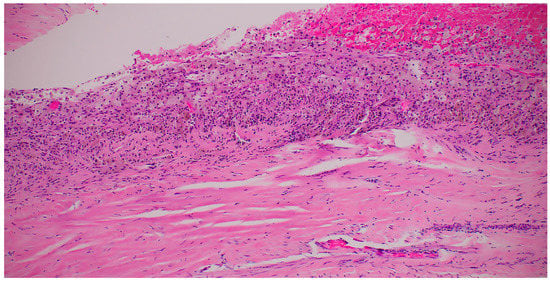

A Large Ovarian Endometrioma Occupying the Abdominal Cavity in a Postmenopausal Patient: A Case Report

2. Case Presentation